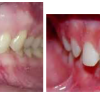

Diasteem

Diasteem – vahe esimeste hammaste vahel. Esineb 50%-l 6-8 aastastel lastel. Kuni 2 mm diasteemi puhul on, peale lateraalse intsisiivi ja silmahamba lõikumist, võimalik diasteemi iseeneslik sulgumine. Diasteem, mille suurus...